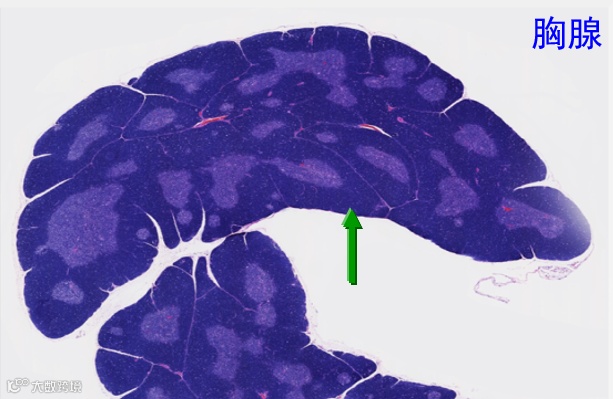

应激可导致淋巴组织内淋巴细胞溶解或解体,如下图所示。

大鼠胸腺 皮质-髓质层交界处急性出血

大鼠胸腺-坏死的淋巴细胞碎片

慢性应激变化可导致淋巴细胞耗尽和淋巴组织萎缩,应正确辨别细胞正常、细胞退化、组织萎缩的差异。